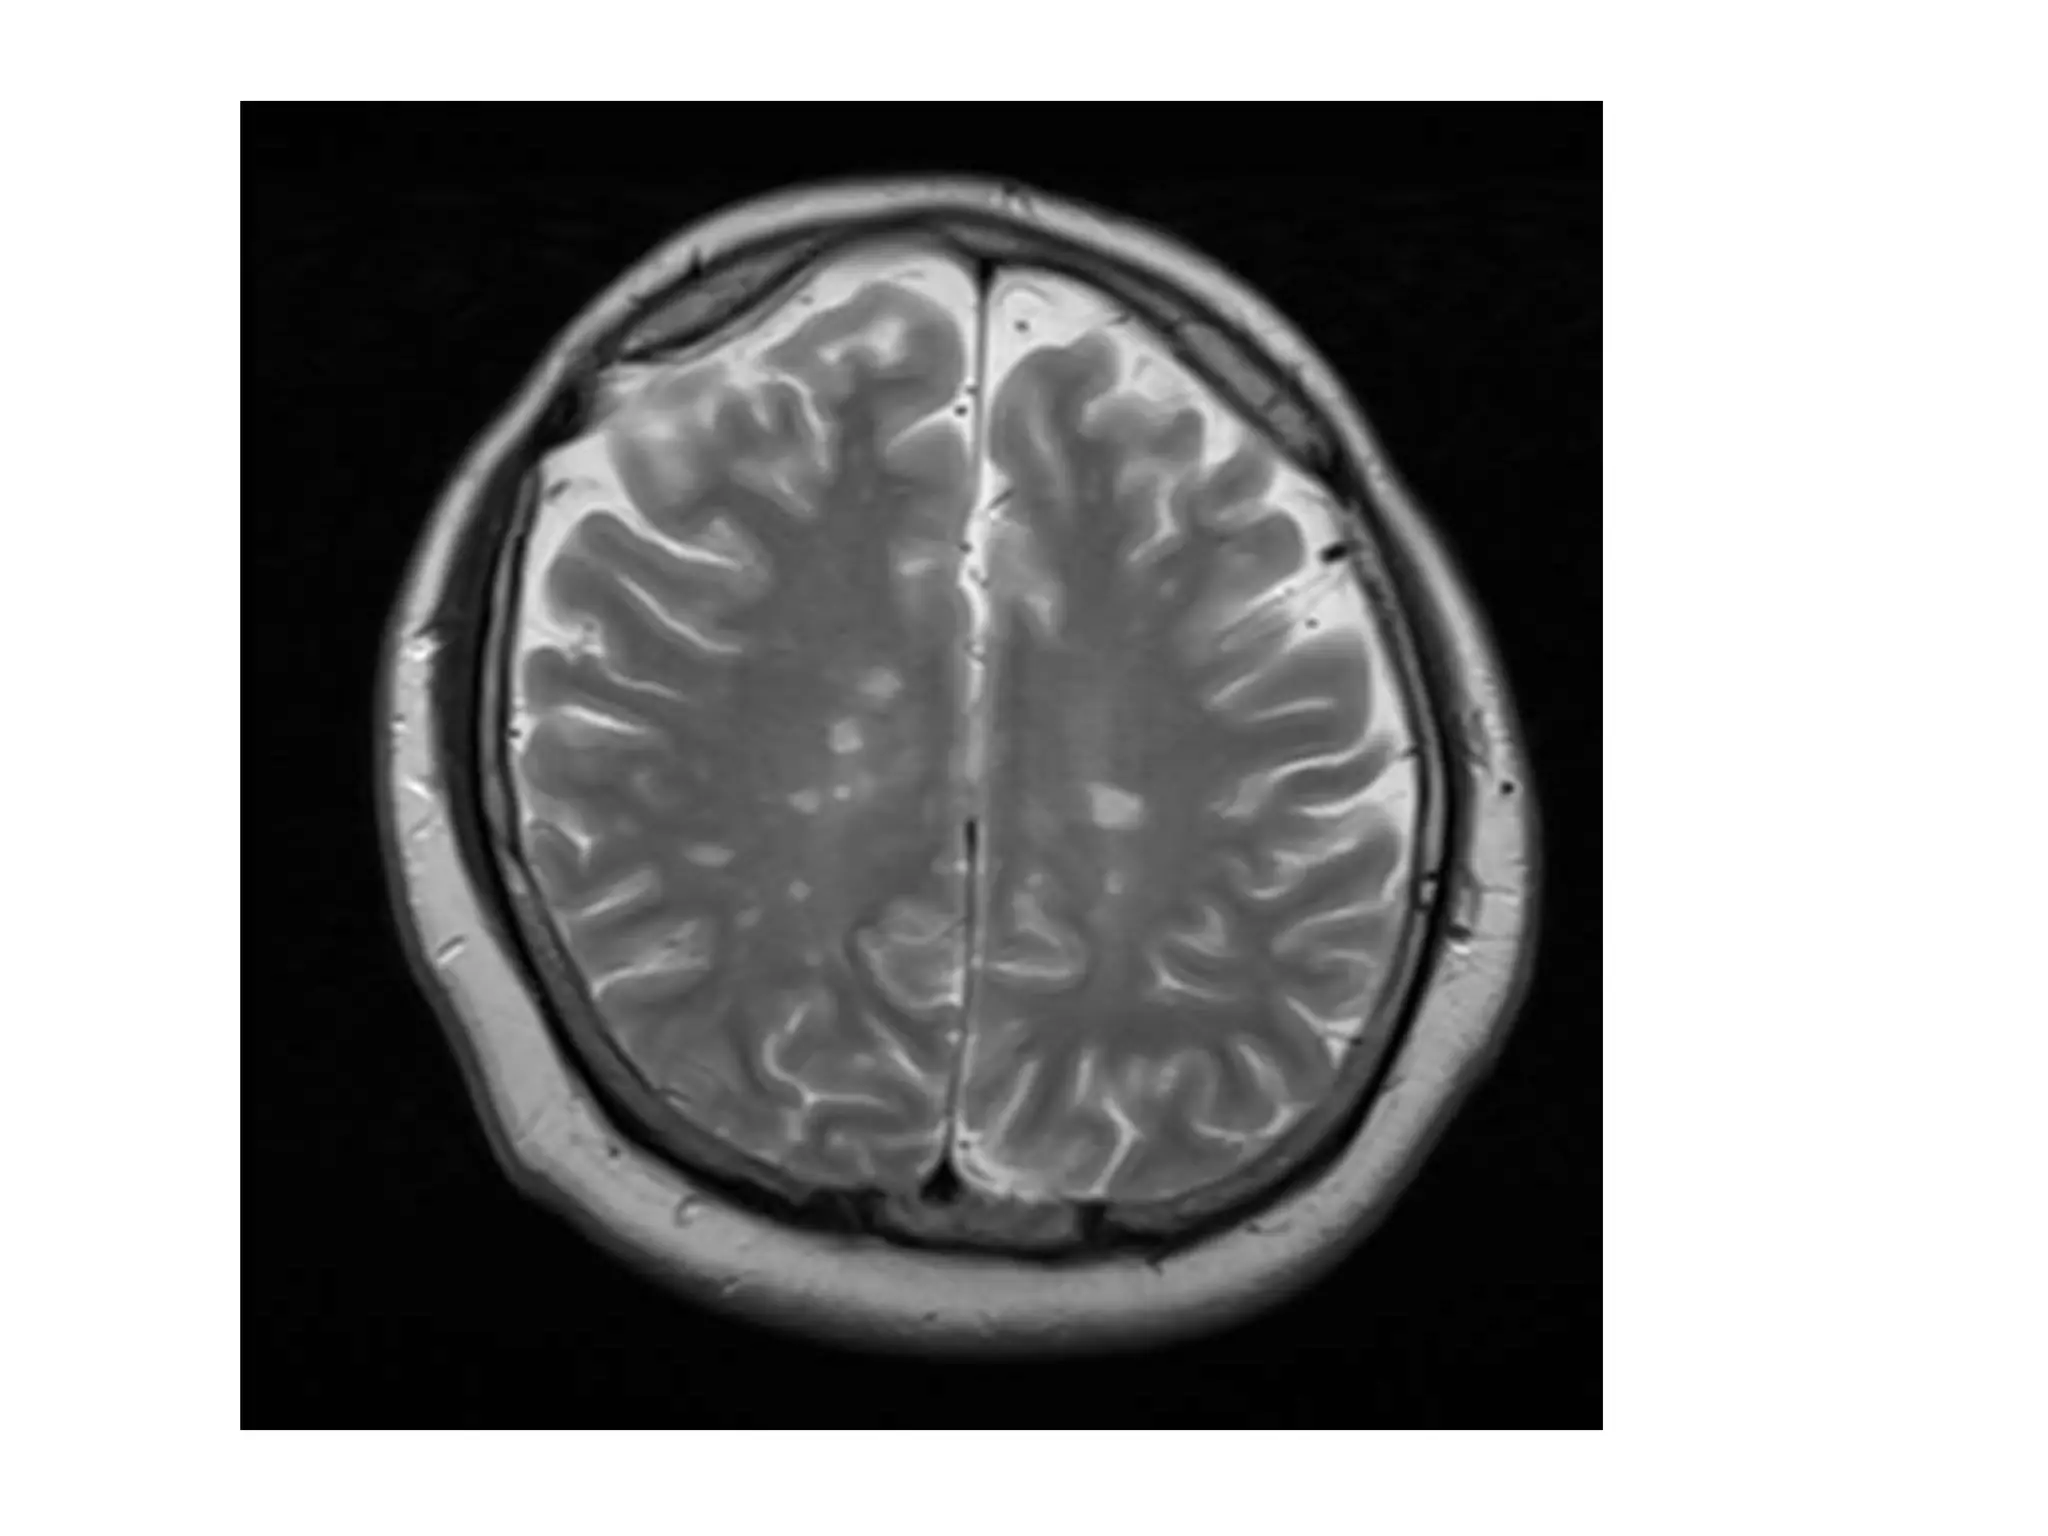

MRI Brain T2WI

MRI Brain DIS

Dissemination in Space

Polman CH et al, Ann Neurol 2011; 69:292–302